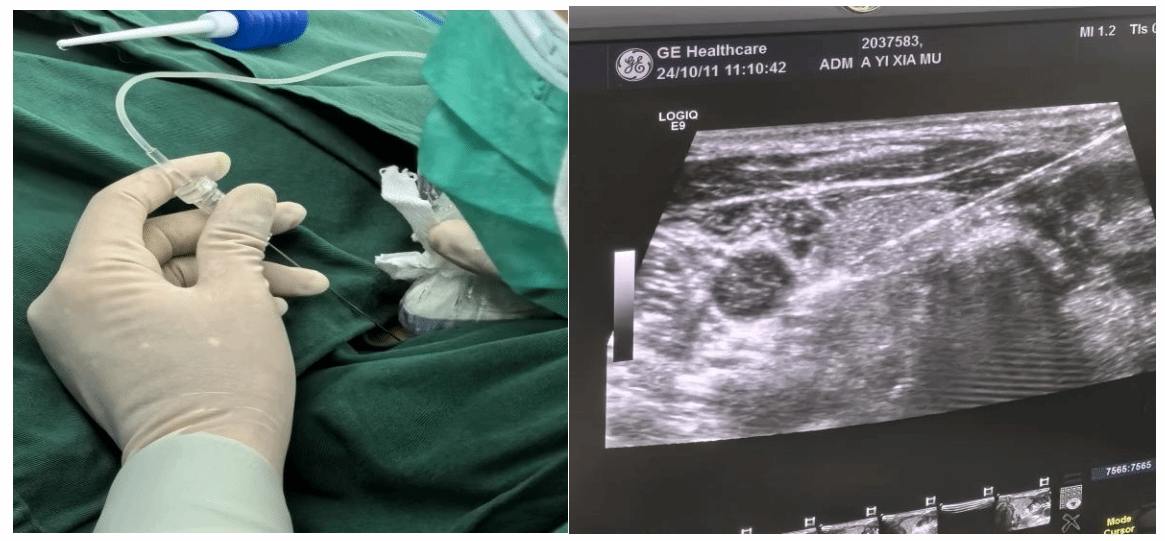

术中细针操作及B超引导视野

目前超声引导下的甲状旁腺病变消融术仅需一根细针便可达到外科手术效果,缓解患者病痛,具有精准、微创、效率高及安全性相对较高等特点,术后患者即刻可以下床活动,骨痛、皮肤瘙痒症状明显缓解。这种新型治疗方式,可以让更多的终末期肾衰竭患者获益。

10月11日,在新疆医科大学第一附属党委副书记、院长陆晨大力支持下,由中日友好医院超声介入科教授于明安指导,新医大一附院肾脏疾病中心副主任、肾病一科主任李素华与腹部超声诊断科主任医师高军喜联合,成功开展超声引导下甲状旁腺射频消融术,仅用一根细“针”就帮助5名终末期肾衰竭患者成功摆脱了困扰多年的继发性甲状旁腺功能亢进症。